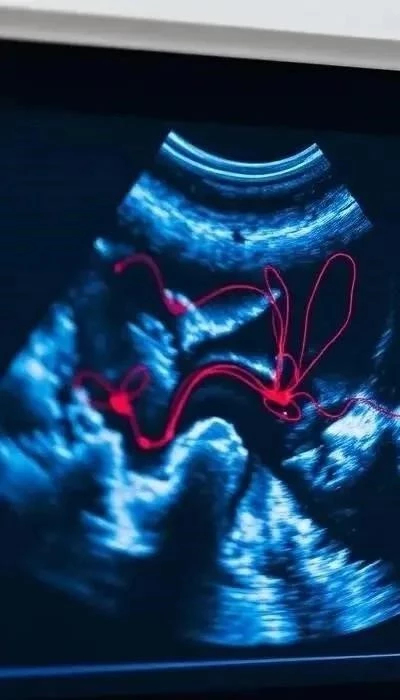

В медицине эффект Доплера широко используется в диагностике. Наиболее известным применением является ультразвуковая доплерография, которая позволяет измерять скорость кровотока в сосудах, диагностировать стенозы, тромбозы и другие патологии сердечно-сосудистой системы. Эхокардиография также активно применяет доплеровский принцип для оценки функций сердца, движения его клапанов и стенок. Это неинвазивный метод, предоставляющий ценную информацию о динамике внутренних органов.